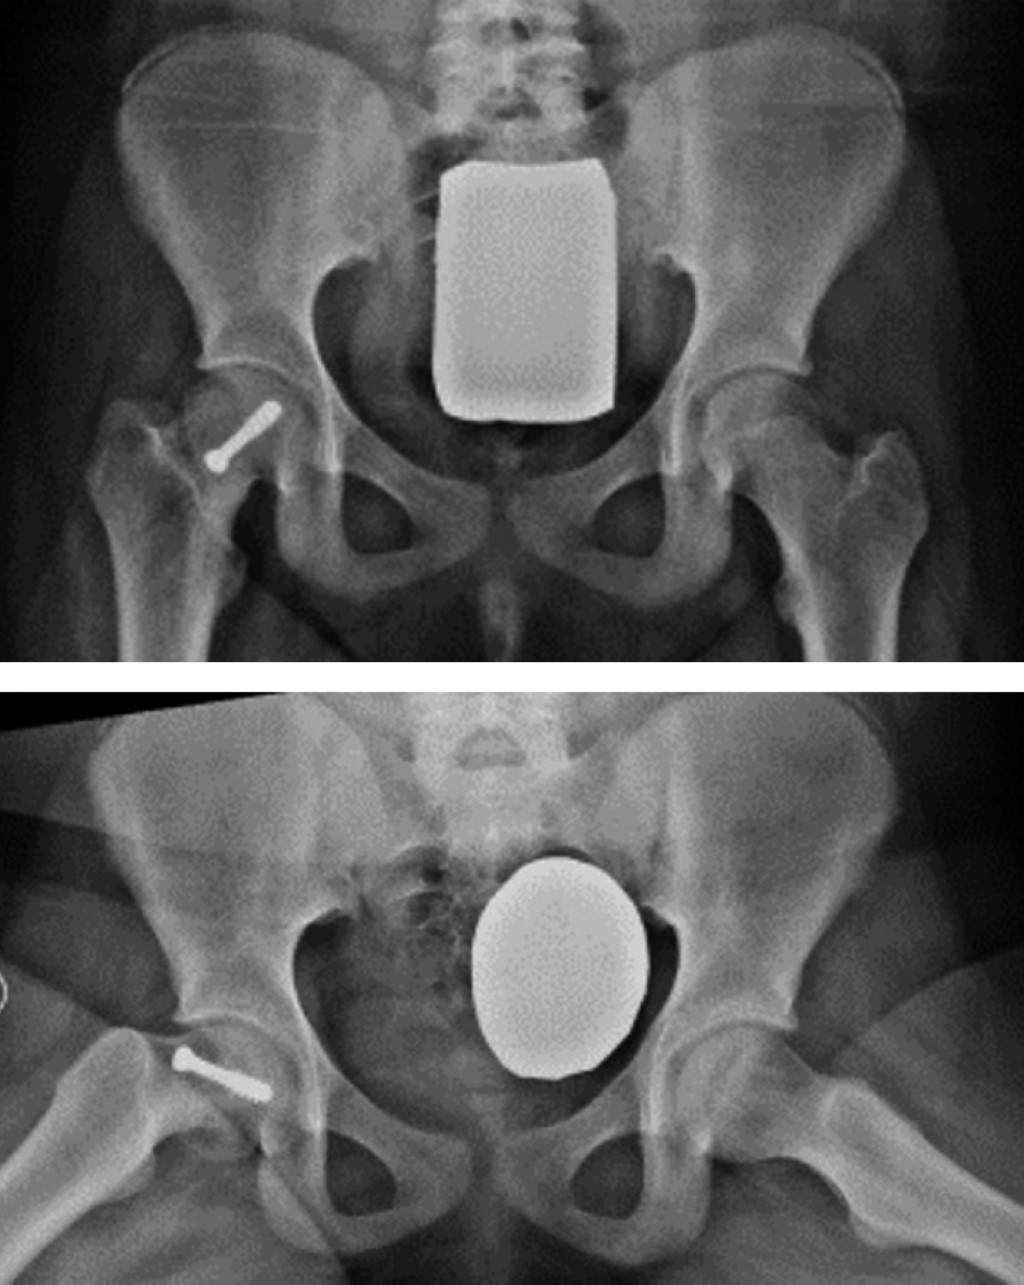

Factors related with bone remodeling of slipped capital femoral epiphysis

Introduction: slipped capital femoral epiphysis (SCFE) is a common condition in pediatric patients that can lead to severe complications if not properly treated. Bone remodeling is crucial for successful recovery, but the factors contributing to complete remodeling (e.g., alpha angle on radiography) are not fully understood. Objectives: to investigate the factors contributing to failed remodeling in patients with SCFE and to describe the diagnostic capability of the alpha angle to predict complete remodeling. Material and methods: 83 patients with SCFE were included. Parameters such as age, laterality, nutritional status, Lodder's classification, and the Southwick angle were evaluated. Comparisons between groups were made to identify factors associated with complete remodeling. Results: complete remodeling was found in 43 patients (51.8%). The presence of an open triradiate cartilage and a lower pre-surgical alpha angle were significantly associated with complete remodeling (p < 0.05). A cut-off value of the alpha angle of 87° showed an AUC of 0.712 (95% CI 0.6-0.82), a sensitivity of 72.5%, and a specificity of 62.8% for predicting complete remodeling. Conclusion: this study identifies the presence of an open triradiate cartilage and a lower alpha angle as important factors in complete remodeling in patients with SCFE. These findings can guide clinical decision-making and emphasize the need for careful evaluation in the treatment of SCFE.

Figure 1

Figure 2